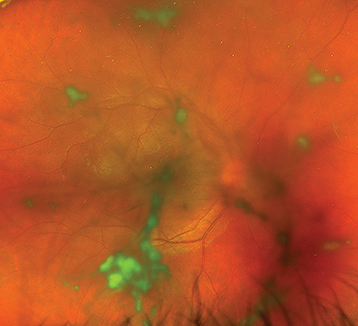

Vitreous cells and cellular aggregates float predominantly in the inferior vitreous (snowballs). Younger patients may present with vitreous hemorrhage. White exudative material over the inferior ora serrata and pars plana (snowbank) is suggestive of pars planitis.

Snowbanking is typically located in the inferior vitreous and can often be seen only with indirect ophthalmoscopy and scleral depression. |

Peripheral retinal vascular sheathing, peripheral neovascularization, mild AC inflammation, CME, posterior subcapsular cataract, band keratopathy, secondary glaucoma, ERM, peripheral retinal cysts, and tractional retinal detachments. Posterior synechiae in pars planitis are uncommon and, if present, usually occur early in the course of the disease. Choroidal neovascularization (CNV) is rare.

(See Figure 12.2.1.)

Pars planitis: Not associated with any other systemic conditions, accounts for 20% to 40% of cases. Characteristic findings include the presence of snowballs ± snowbanks. Occurs in young men and women in early teens to young adulthood. CME is the most common cause of vision loss. Peripheral nonperfusion and subsequent neovascularization and vitreous hemorrhage may cause acute vision loss.

Sarcoidosis: May have associated phlebitis which classically appears as candle wax drippings. May also have snowballs. Syphilis: See 12.10, Syphilis.